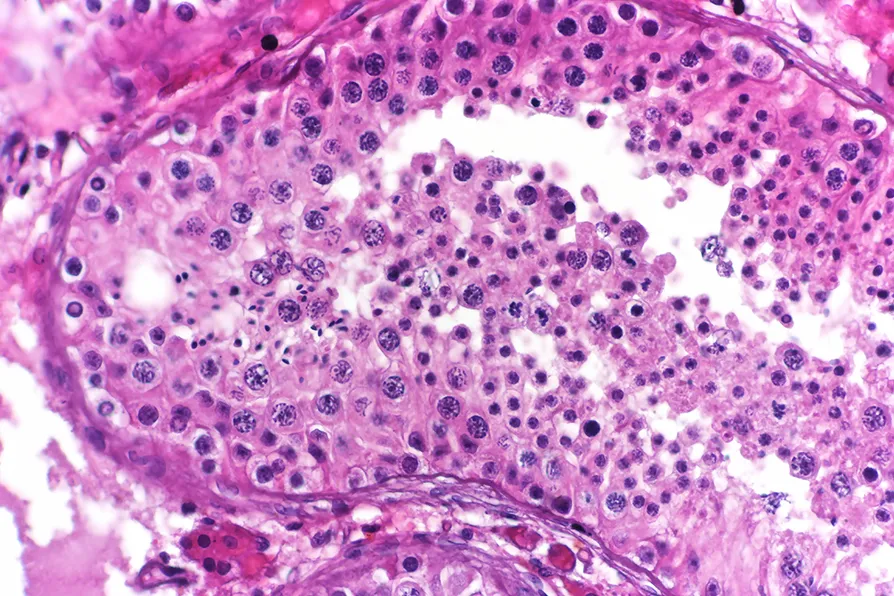

Most of these mutations are harmless, but some of them can have negative effects. For example, they can make a cell start to divide more quickly than it would otherwise, creating a lump of related cells that grows where it shouldn’t. This is the problem of cancer.

These mutations are retained because of ongoing evolution inside the population of sperm cells. Natural selection within this population will favour sperm cells that are better at dividing more quickly, and over time these mutated sperm cells will have more descendants.

Unfortunately, these mutations are often associated with a higher rate of cancers and developmental disorders, which makes sense given the “cancer-like” property of faster division.

This means older sperm cells carry more risk of developmental disorders. The study’s estimate is that 3-5 per cent of sperm from men older than 50 carry a potentially dangerous mutation.